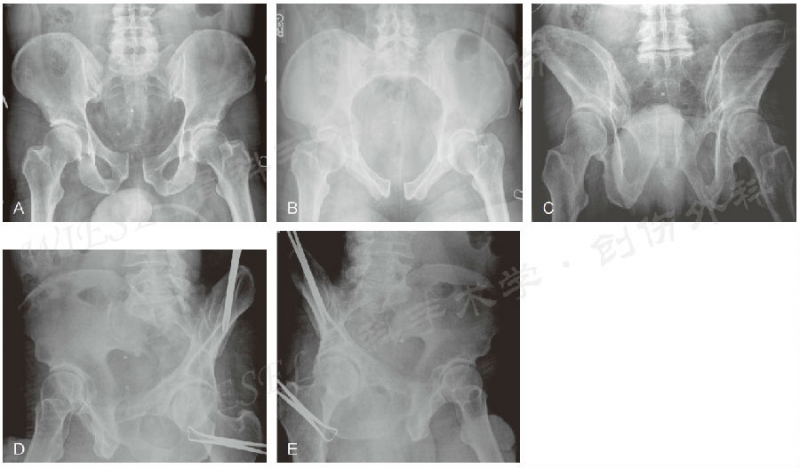

图5 A~E.一例骨盆创伤、耻骨联合增宽患者的骨盆前后位(A)、入口位(B)、出口位(C) 以及Judet位(D、E)影像(经允许引自Jodi Siegel,MD&David Templeman,MD)